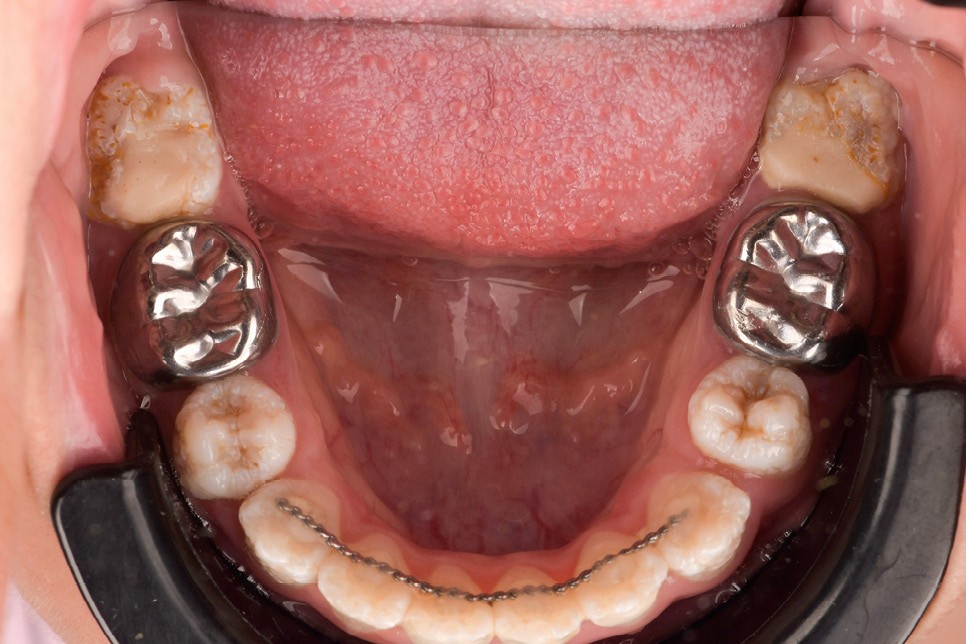

Lors de l’arrivée de la patiente, un examen clinique au fauteuil est effectué, complété par une empreinte numérique permettant l’enregistrement précis des arcades dentaires et de l’occlusion existante. Cet examen initial met en évidence une pathologie de type amélogenèse imparfaite. On note également la présence de couronnes métalliques au niveau des premières molaires, ainsi que de multiples restaurations, notamment au niveau des dernières molaires (fig. 1 à 4).

La première étape décisionnelle repose sur une analyse esthétique du visage et du sourire, réalisée à l’aide du logiciel SmileCloud. Cette analyse permet d’évaluer les proportions dentaires, la ligne du sourire et les rapports dento-labiaux. Elle confirme que le traitement vise à la fois la protection d’un émail de mauvaise qualité et l’amélioration de l’esthétique globale, avec notamment une optimisation des proportions dentaires (fig. 5 et 6).